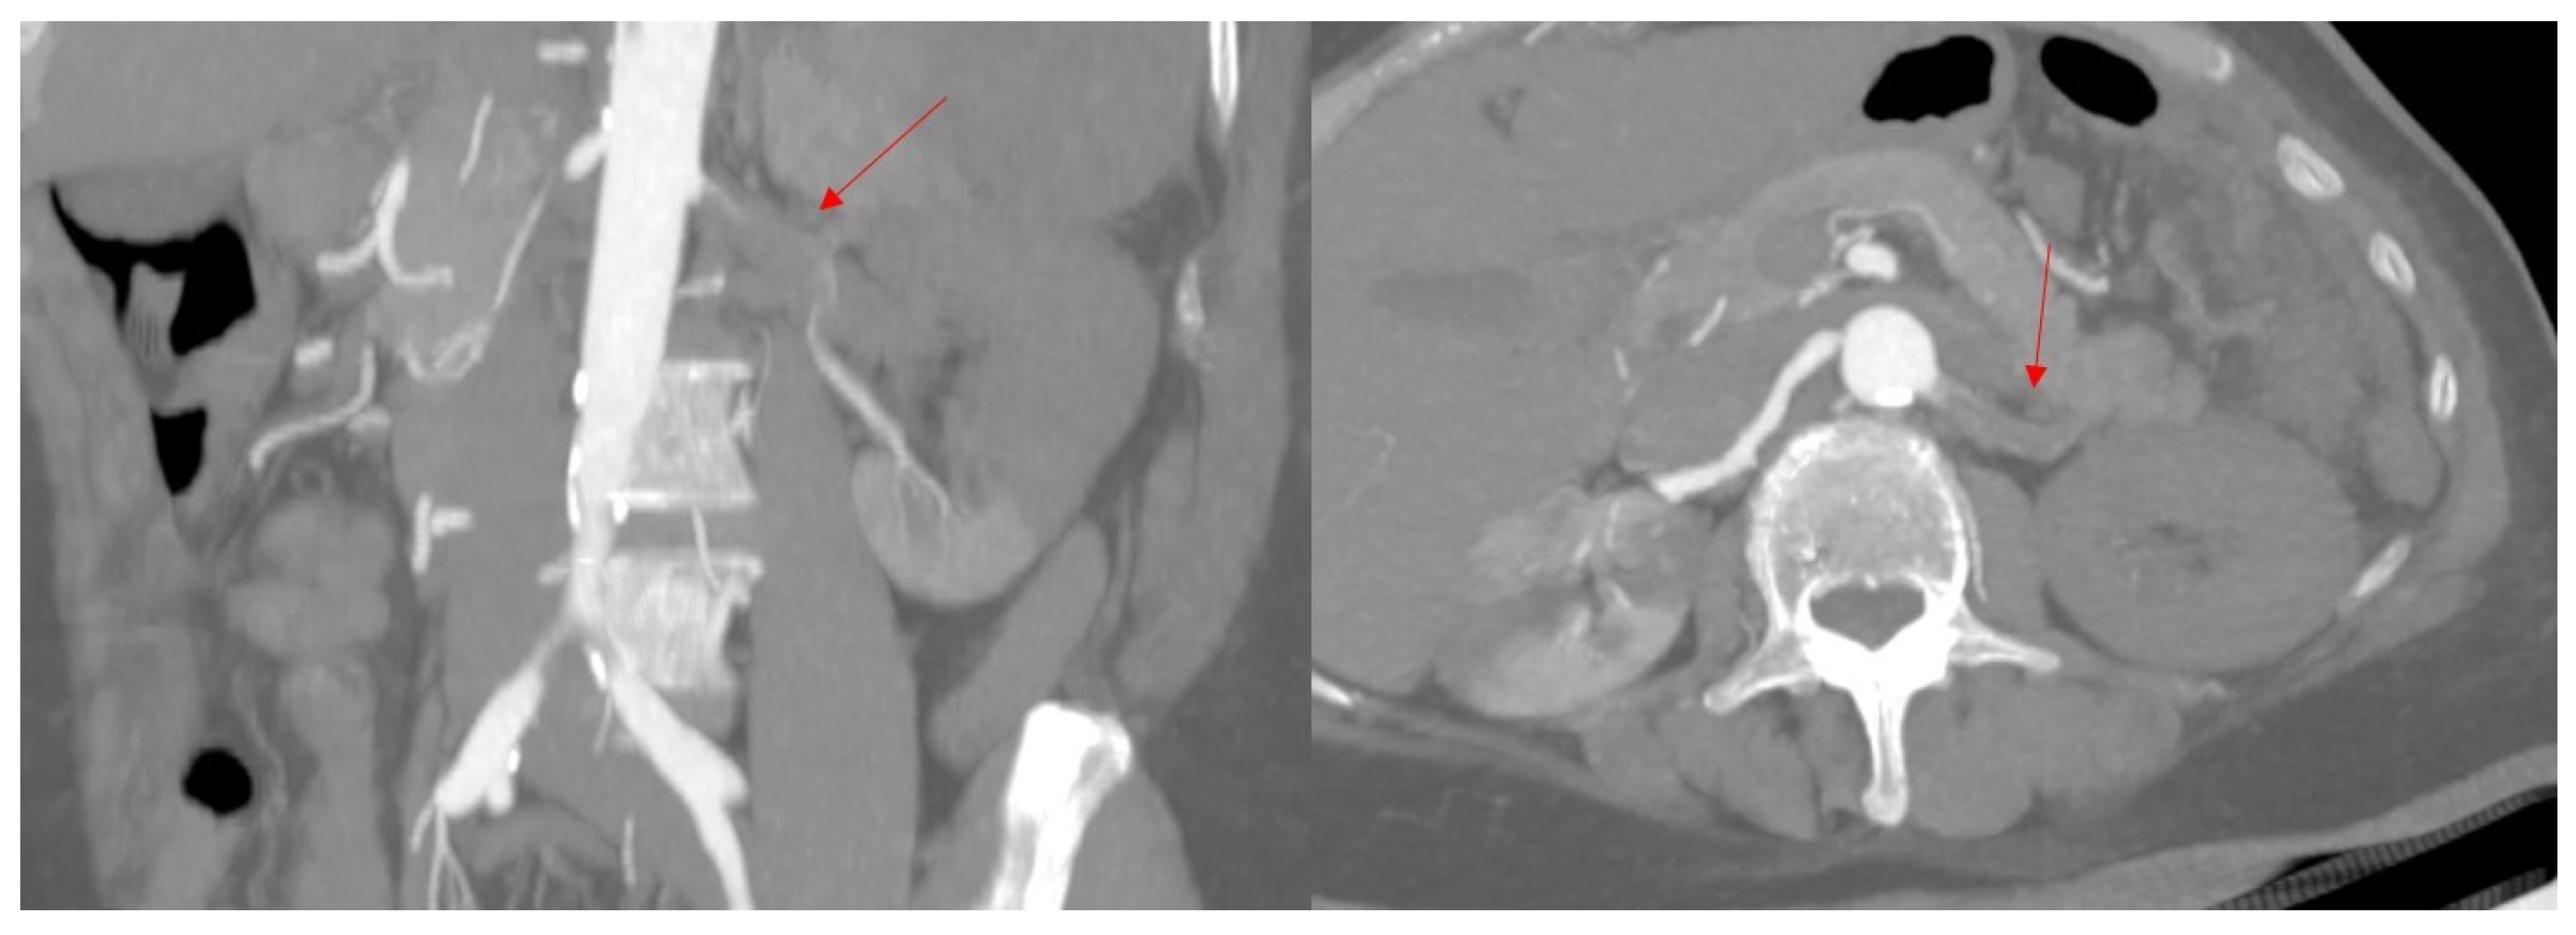

2. Case Presentation